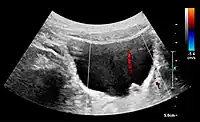

Doppler ultrasonography of the kidney is widely used, and the vessels are easily depicted by the color Doppler technique in order to evaluate perfusion. Applying spectral Doppler to the renal artery and selected interlobular arteries, peak systolic velocities, resistive index, and acceleration curves can be estimated (Figure 4) (e.g., peak systolic velocity of the renal artery above 180 cm/s is a predictor of renal artery stenosis of more than 60%, and a resistive index, which is a calculated from peak systolic and end systolic velocity, above 0.70 is indicative of abnormal renovascular resistance).[1]

Figure 21. Left hydroureter with ureteric jet. No stone is visible. The red color in the color box represents motion towards the transducer as defined by the color bar.[1]